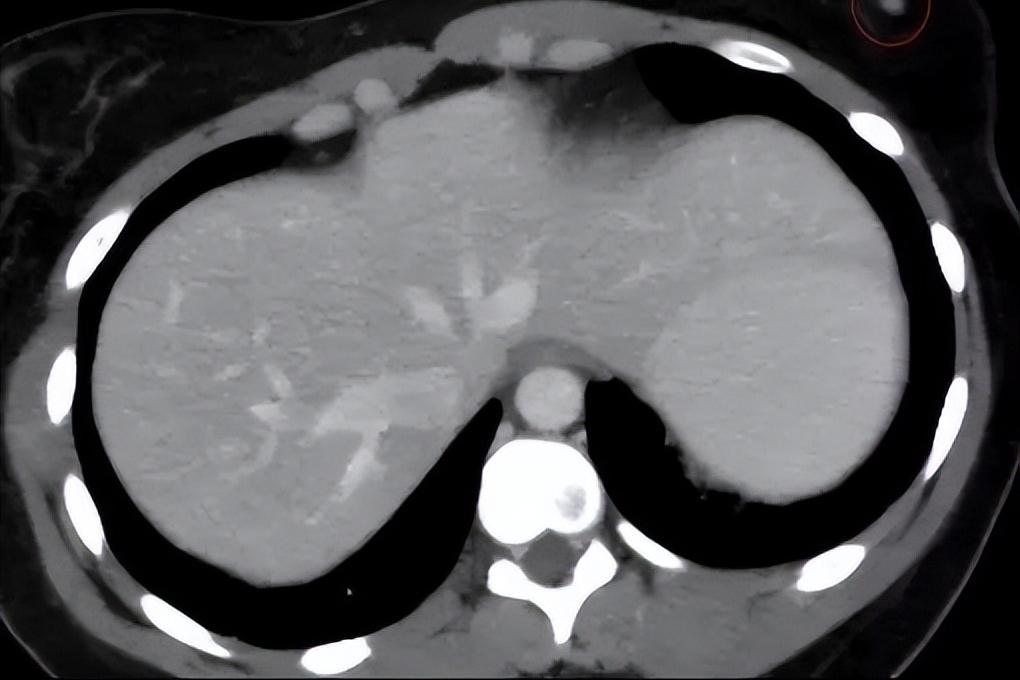

一系列检查完毕,确诊小彭患上的是先天性无阴道症合并先天性无子宫,也就是民间所说的石女,小彭一直不来月经也是因为这种病造成的原发性闭经。

对于这部分患者来说,她们出生就没有阴道,大多数患者只有一个始基子宫甚至没有子宫。此外,一部分更严重的患者也会出现单侧肾发育不全、脊柱畸形、颜面不对称、听力缺陷甚至法洛四联症等其他部位的先天畸形。